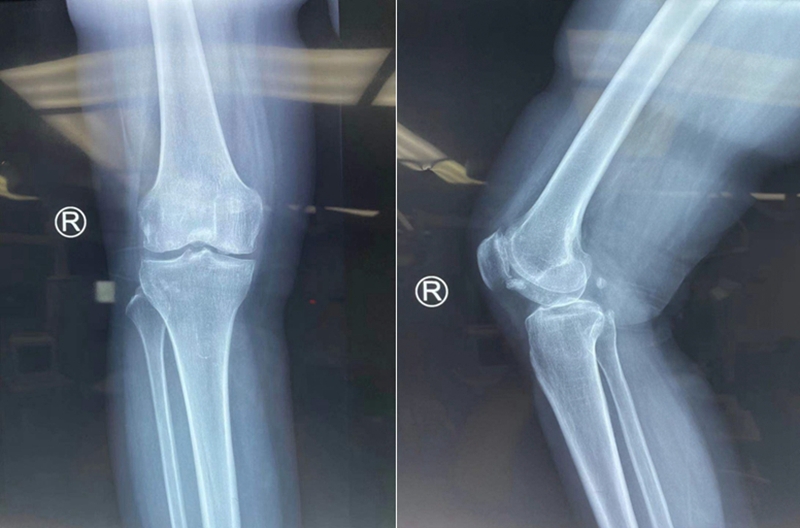

患者女性,56岁,右膝关节疼痛,X线显示关节间隙基本正常,整体力线轻度内翻畸形,关节内游离体,核磁显示内外侧软骨病变,内外侧半月板完整。由于担心外侧软骨退变,门诊计划行单纯关节镜清理,取游离体。不做截骨术减压内侧病变。

术前再次阅片

MR显示外侧负重区良好,外侧软骨磨损位于非负重区